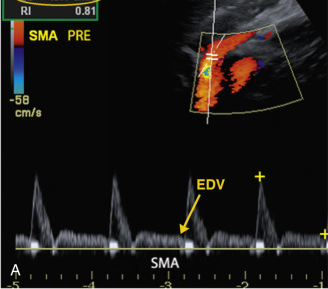

A) Las ondas Doppler espectrales de la arteria mesentérica superior (AMS ) en ayunas muestran un patrón de flujo de alta resistencia

(B) La imagen Doppler espectral de la AMS en estado posprandial de este paciente muestra un aumento en el intervalo de la velocidad sistólica máxima (VSM ) y la VTD. Obsérvese el aumento de la VTD a 55 cm/s.